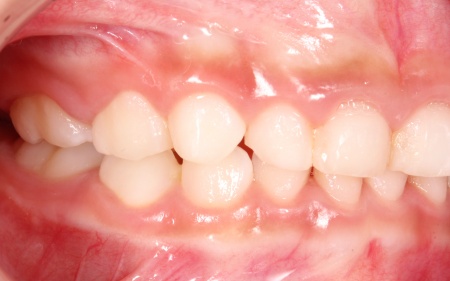

治療後

治療中は、スクリューを少しずつ回すことで顎の骨が徐々に横方向に拡大されていき、永久歯が生えるためのスペースを十分に確保することができました。

拡大治療が完了したあとは、顎の状態を安定させるためのリテーナー(保定装置)を装着し、治療を終了しています。